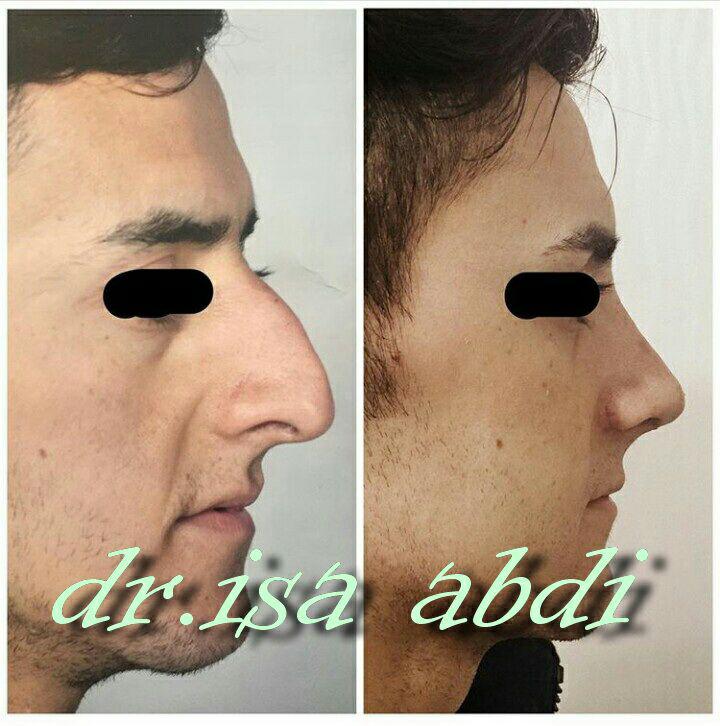

دکتر عیسی عبدی در رشت

دکتر عیسی عبدی در رشت

– متخصص جراحی فک , پلاستیک صورت و بینی

دکتر عیسی عبدی در رشت

جراحی فک , پلاستیک , صورت وبینی